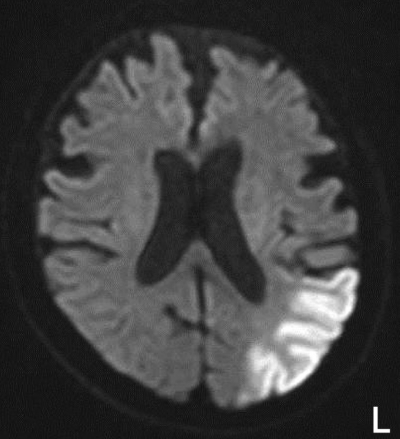

胸部エックス線写真で心胸郭比58 %。心電図で心房細動を認める。頭部MRIの拡散強調像を別に示す。